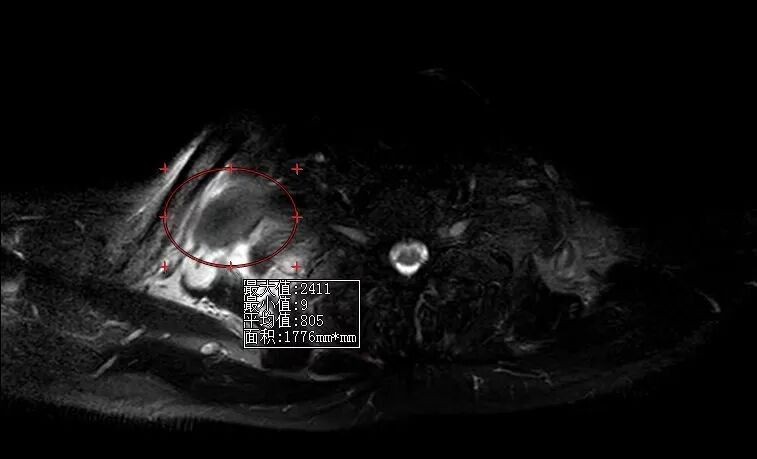

在史进主任的指导下,孙倩主治医师、胡雪婷住院医师详细询问病史、细致体格检查,凭借扎实的全科诊疗功底与严谨的临床思维,果断排除脑梗死及颈椎病变,高度怀疑为臂丛神经损伤,并及时为患者完善针对性臂丛神经磁共振检查。

检查结果证实了医师的判断:老人右侧臂丛神经被一巨大包块长期压迫,正是导致肢体麻木无力的“元凶”。明确病因后,全科医学科立即启动多学科协作,积极联系骨科专家、主任医师李波团队制定手术方案,顺利为老人手术解除神经压迫,从根源上解决了困扰他8个月的痛苦。